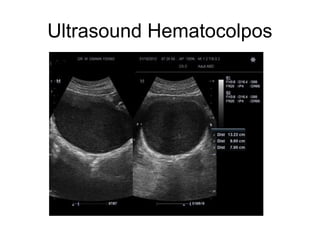

Ultrasound Hematocolpos

• USG reveals a thick walled cystic

mass either due to obstructed

vagina or obstructed uterus with

low level internal echoes due to

blood.